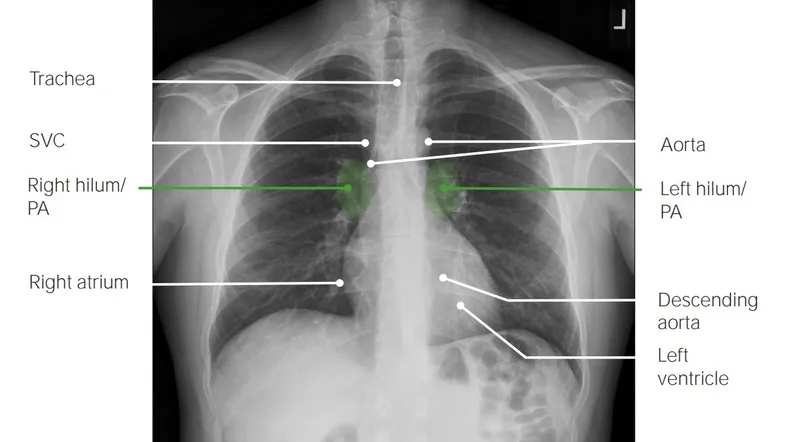

Mediastinum & Heart - Central Command

- Cardiac Silhouette:

- PA Borders:

- Right: SVC, RA.

- Left: Aortic Knob, MPA, LAA, LV.

- Lateral Borders:

- Anterior: RV.

- Posterior: LA, LV.

- Hila:

- Left hilum typically higher (≤ 2.5 cm) than right.

- Contents: Pulmonary vessels, bronchi, nodes.